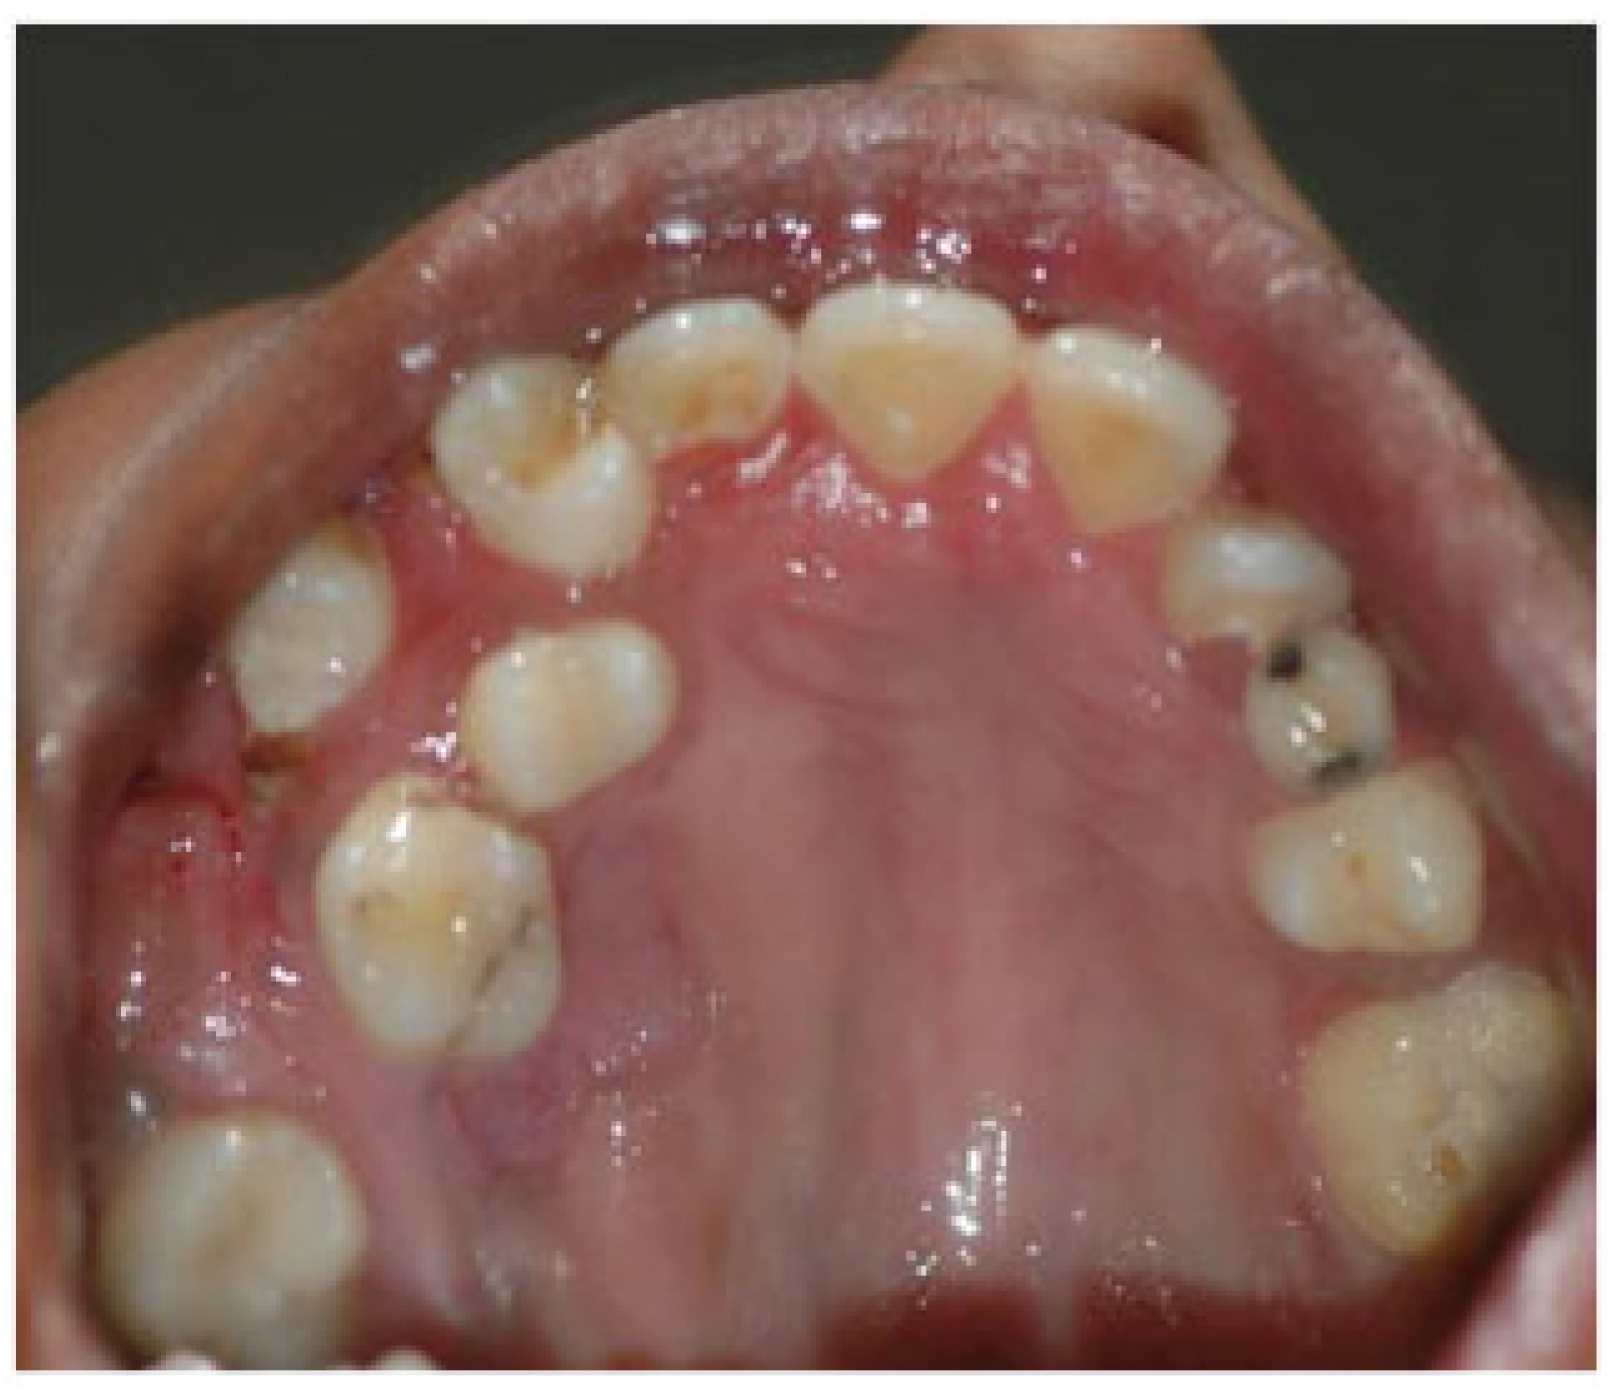

- Incomplete Tessier 7 soft tissue facial cleft and a complete skeletal Tessier 7 cleft on the right side

- Incomplete Tessier 5 skeletal and soft tissue Tessier 6 facial cleft on the left side